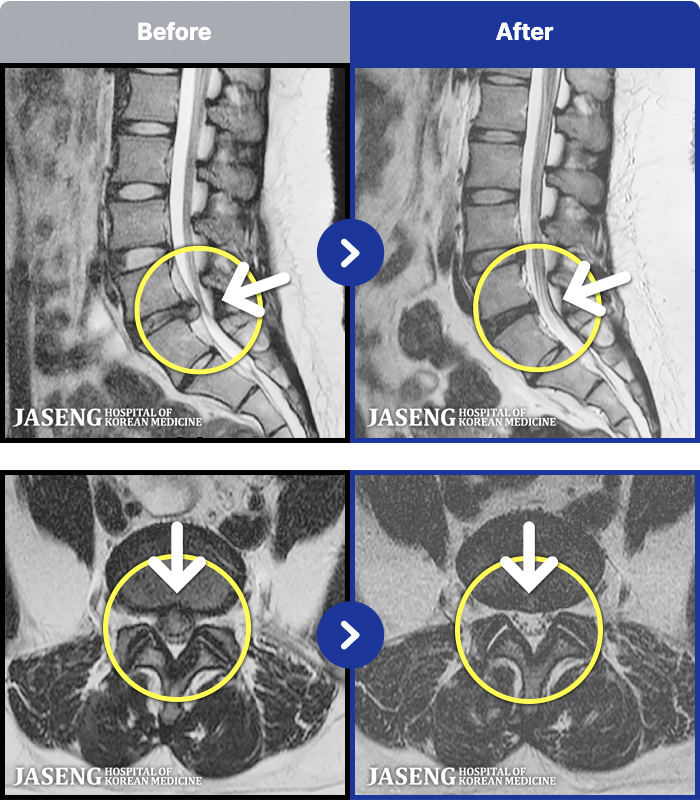

- MRI ġ

MRI ġ

56 MRI ũ ʸ Ȯϼ.

㸮 ϻ .

ǿ

Ȼ

ȯ

㸮ũ

[Ȼ] 23.03.13~24.05.08

ȯںп Ǹ ǿ ԿǾ, ο ġ ۿ Ƿ ġḦ Ͻñ ٶϴ.